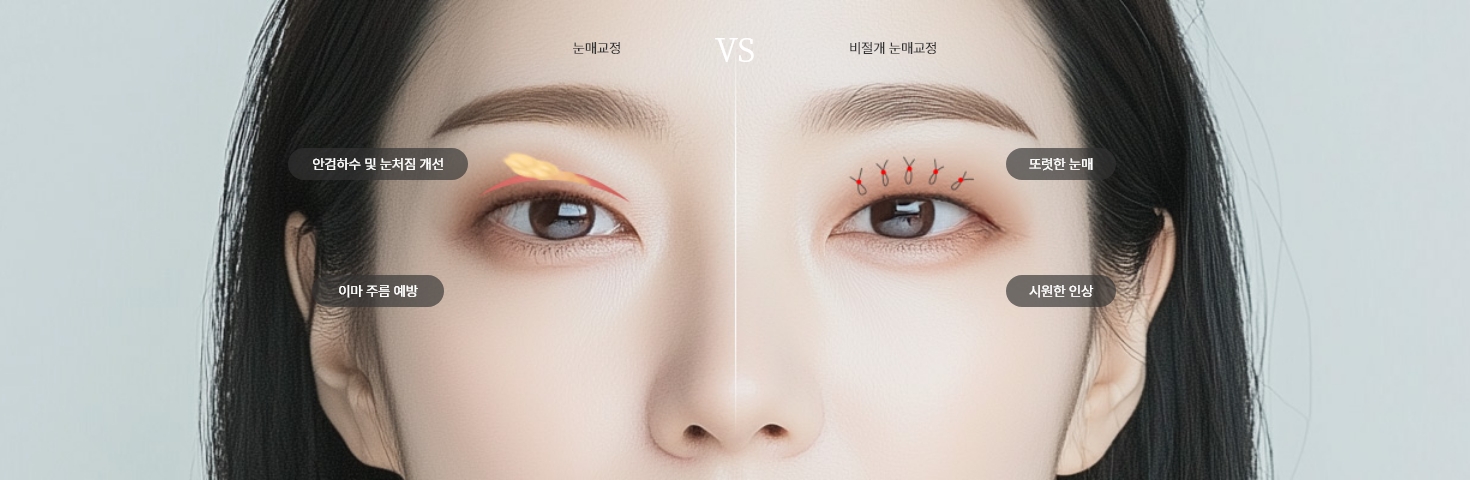

<li><a href="/bbs/board.php?bo_table=eye&wr_id=4">비절개 눈매교정</a></li>

<li class="on"><a href="/bbs/board.php?bo_table=eye&wr_id=12">절개 눈매교정</a></li>

<h1>절개 눈매교정</h1>

<div class="en">Ptosis Correction</div>

<p>

과거에는 안검하수를 주로 쌍꺼풀 수술로 개선했지만 성형술이 발달하면서 필요한 절개, 혹은 비절개를 통한 눈매교정 수술을 진행하여 보다 크고 또렷하게 눈매 개선이 가능해졌습니다.